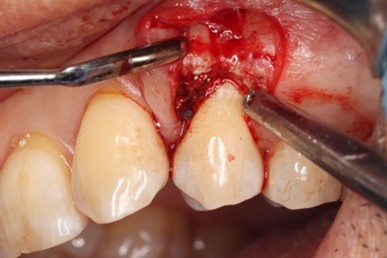

治療中

エムドゲイン®サイトランス®を填入し、レーザーにて血餅形成、縫合

歯周基本治療後に再評価し、ポケットが残存したのでEr:YAGレーザーを併用した歯周組織再生療法(エムドゲイン® 、サイトランス®を使用)を行ったケース

歯周病の好発部位である上顎第一小臼歯近心面における骨吸収に対して再生療法を行ったケース。一般的に根面溝という溝があり歯石の沈着が生じやすい。また溝の存在により術後に歯肉と歯根の付着が生じにくいため、今回はEr:YAGレーザーにて血餅形成を行い組織の安定化を図った。